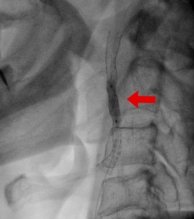

頚動脈ステント留置術

脳梗塞や一過性脳虚血発作の原因となる頚動脈狭窄に対する治療です。内頚動脈に細い針金を通して、風船(バルーン)で病変を開大させます。ステントという金属の支持器具を留置します。病変の長さ、形態によっては外科的手術(内膜はく離術)を選択することがあります。

治療の前後でMRI検査を行い、脳梗塞や過かん流症候群などの合併症の有無を確認します。残念ながら全国的な調査では4-5%の合併症が報告されています。当院では脳神経外科意思と協力して患者さんに合った治療法、合併症の治療を行っています。

治療前

治療中

治療後